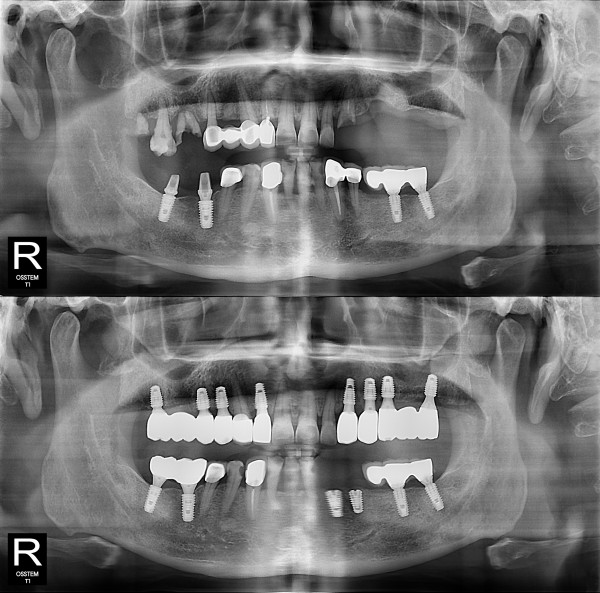

임플란트 뼈이식 + 임플란트